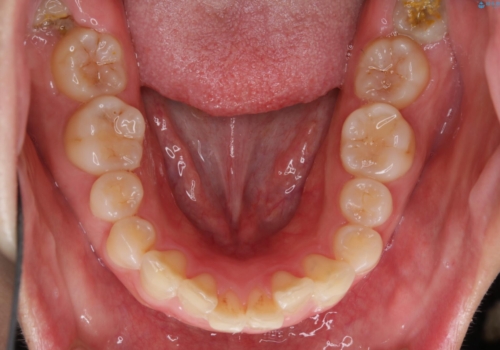

- 前歯のがたつきが気になるとご相談にいらした方です。当初は前歯の部分矯正をご希望されていましたが、全体的に整えることで審美的、機能的な歯並びとなりました。

当初は上顎前歯のみの部分矯正をご希望されていましたが、部分的に前歯のみを並べると出っ歯感がつよくなり、食事もしづらくなる可能性をお伝えしました。全顎的な矯正治療により、審美的、機能的な歯並びとなりました。